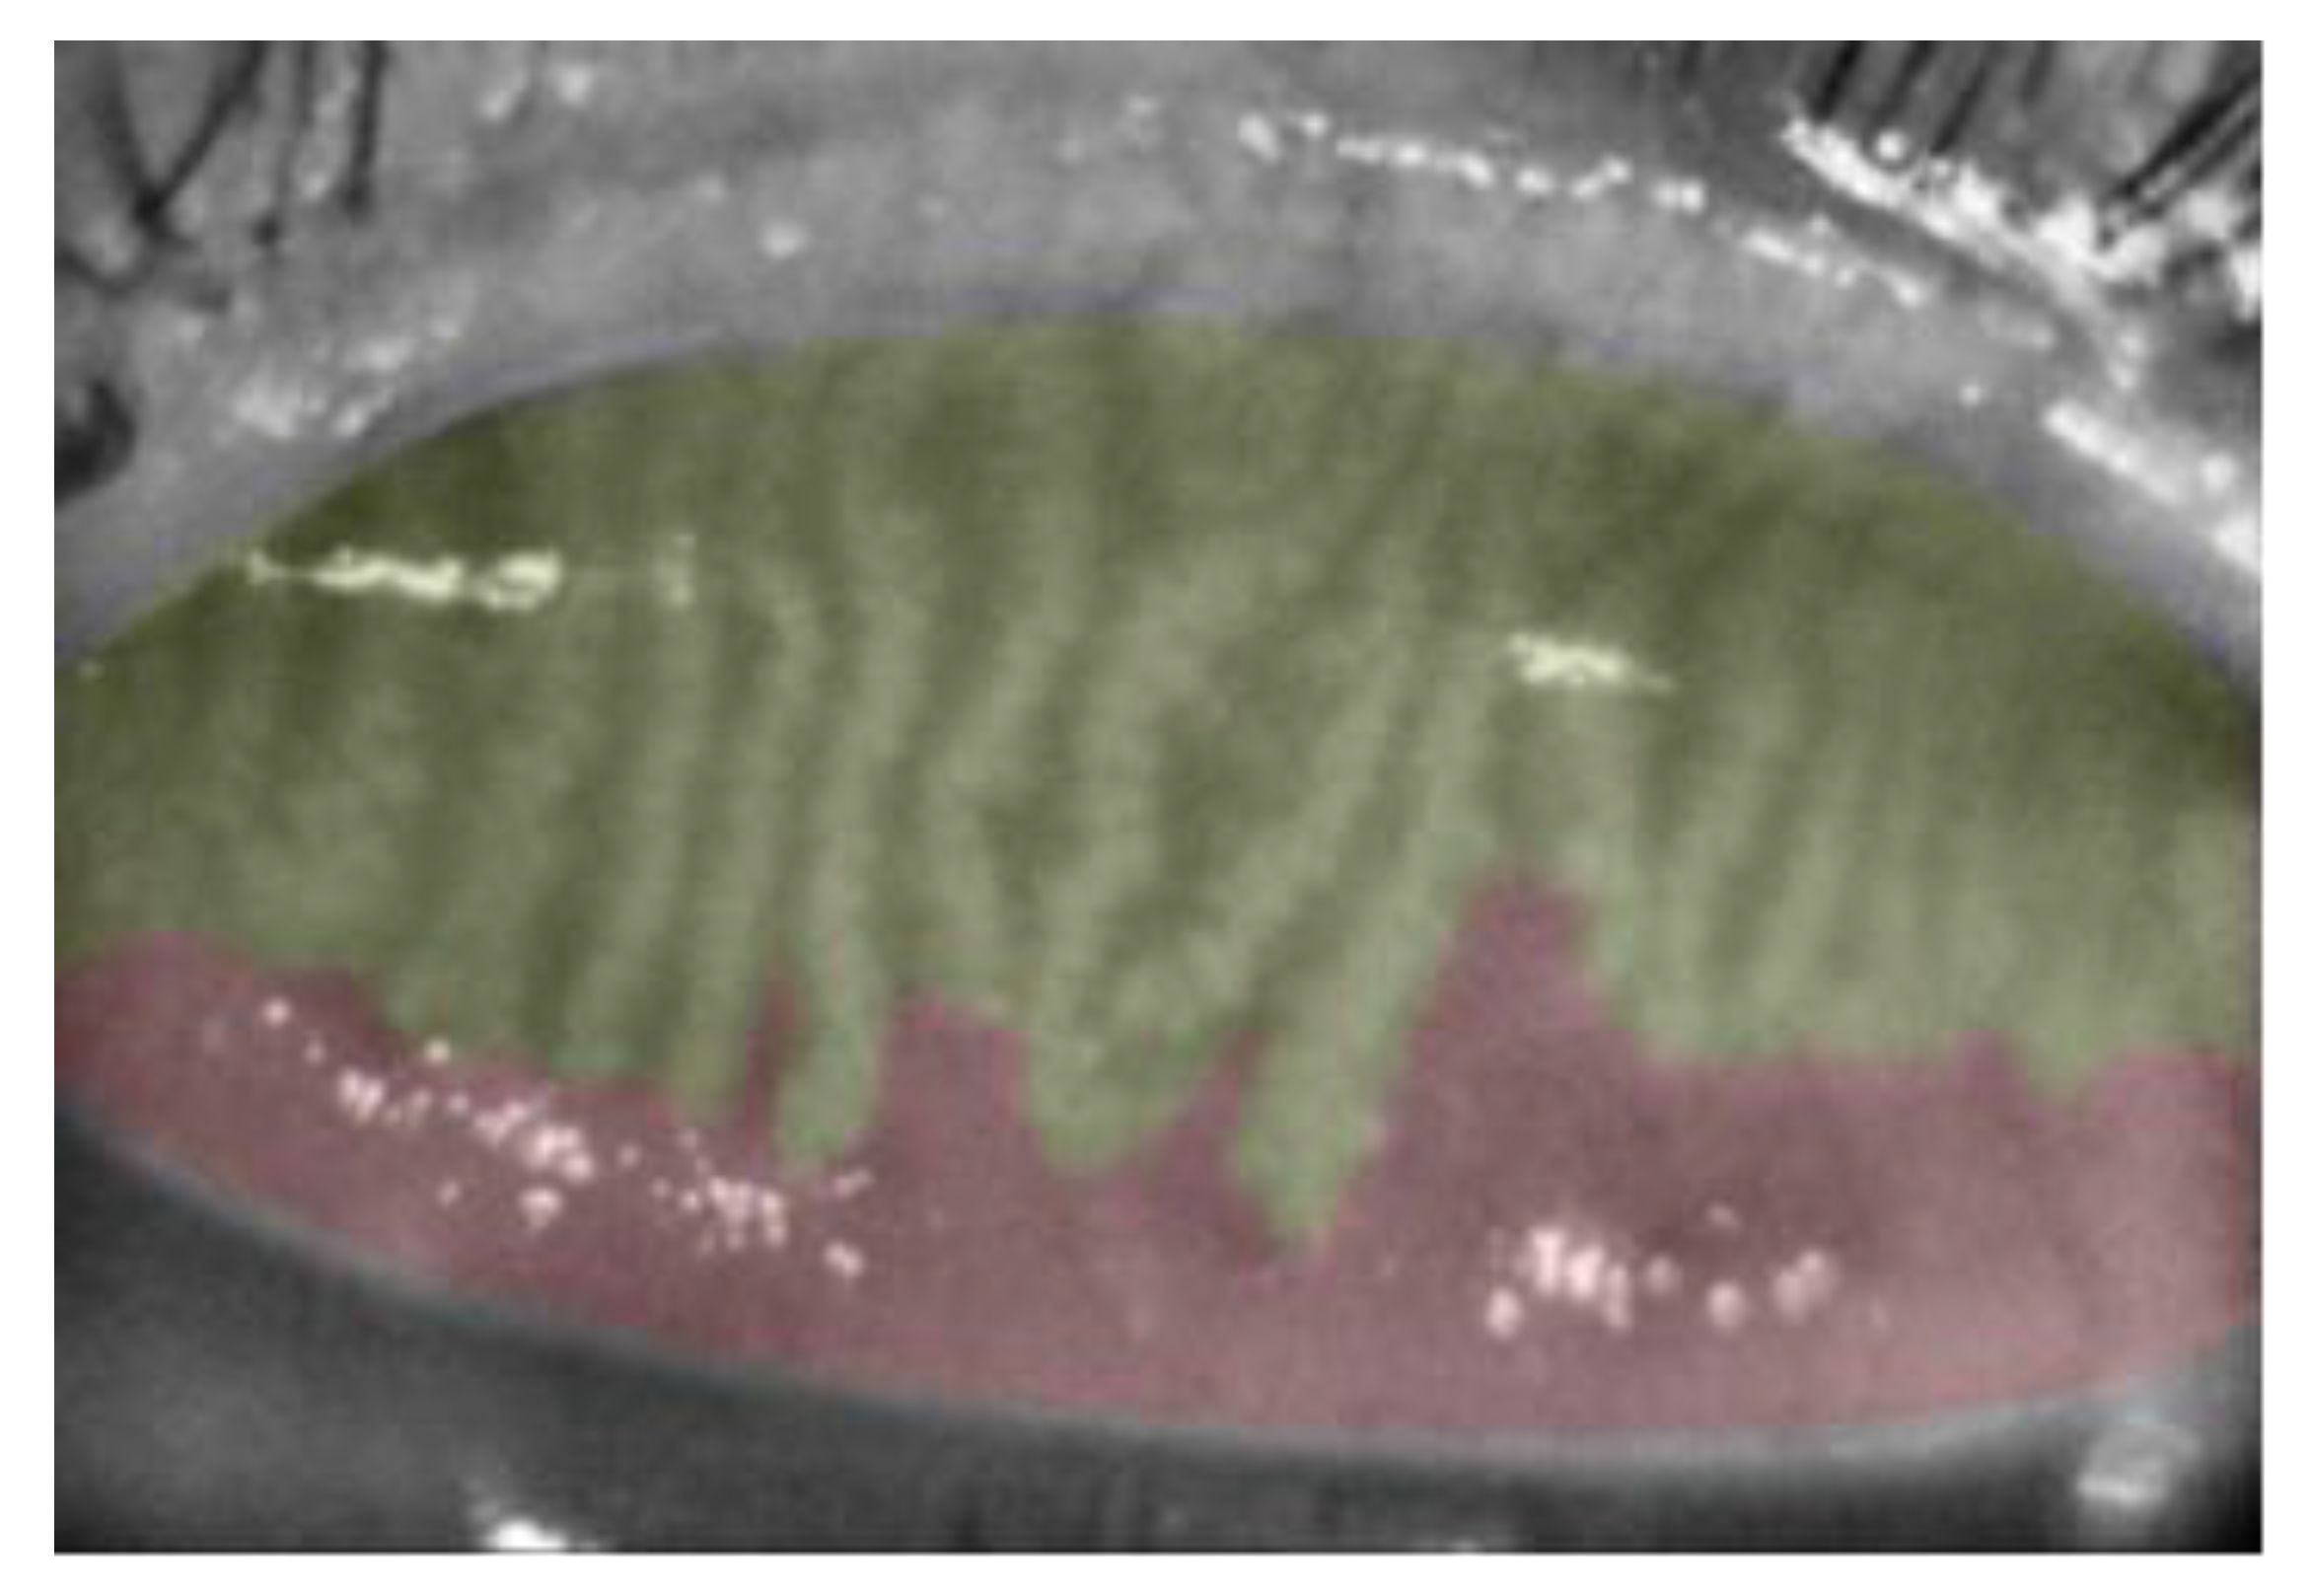

3.2. Meibography Analysis